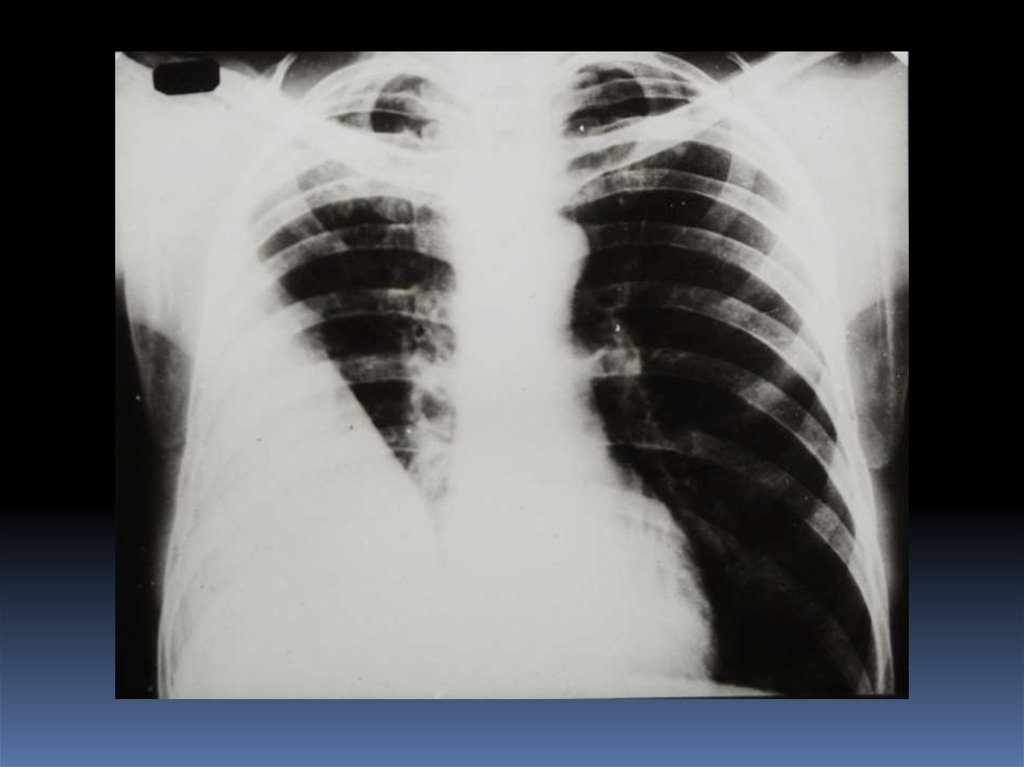

5. Проведение рентгеноскопического исследования раненого.

6. Проведение рентгенографического исследования раненого.

7. Виды травматического повреждения грудной клетки:

пневмоторакс;

гемоторакс;

гемопневмоторакс;

внутрилегочные гематомы;

дисковидные ателектазы;

посттравматические пневмонии.